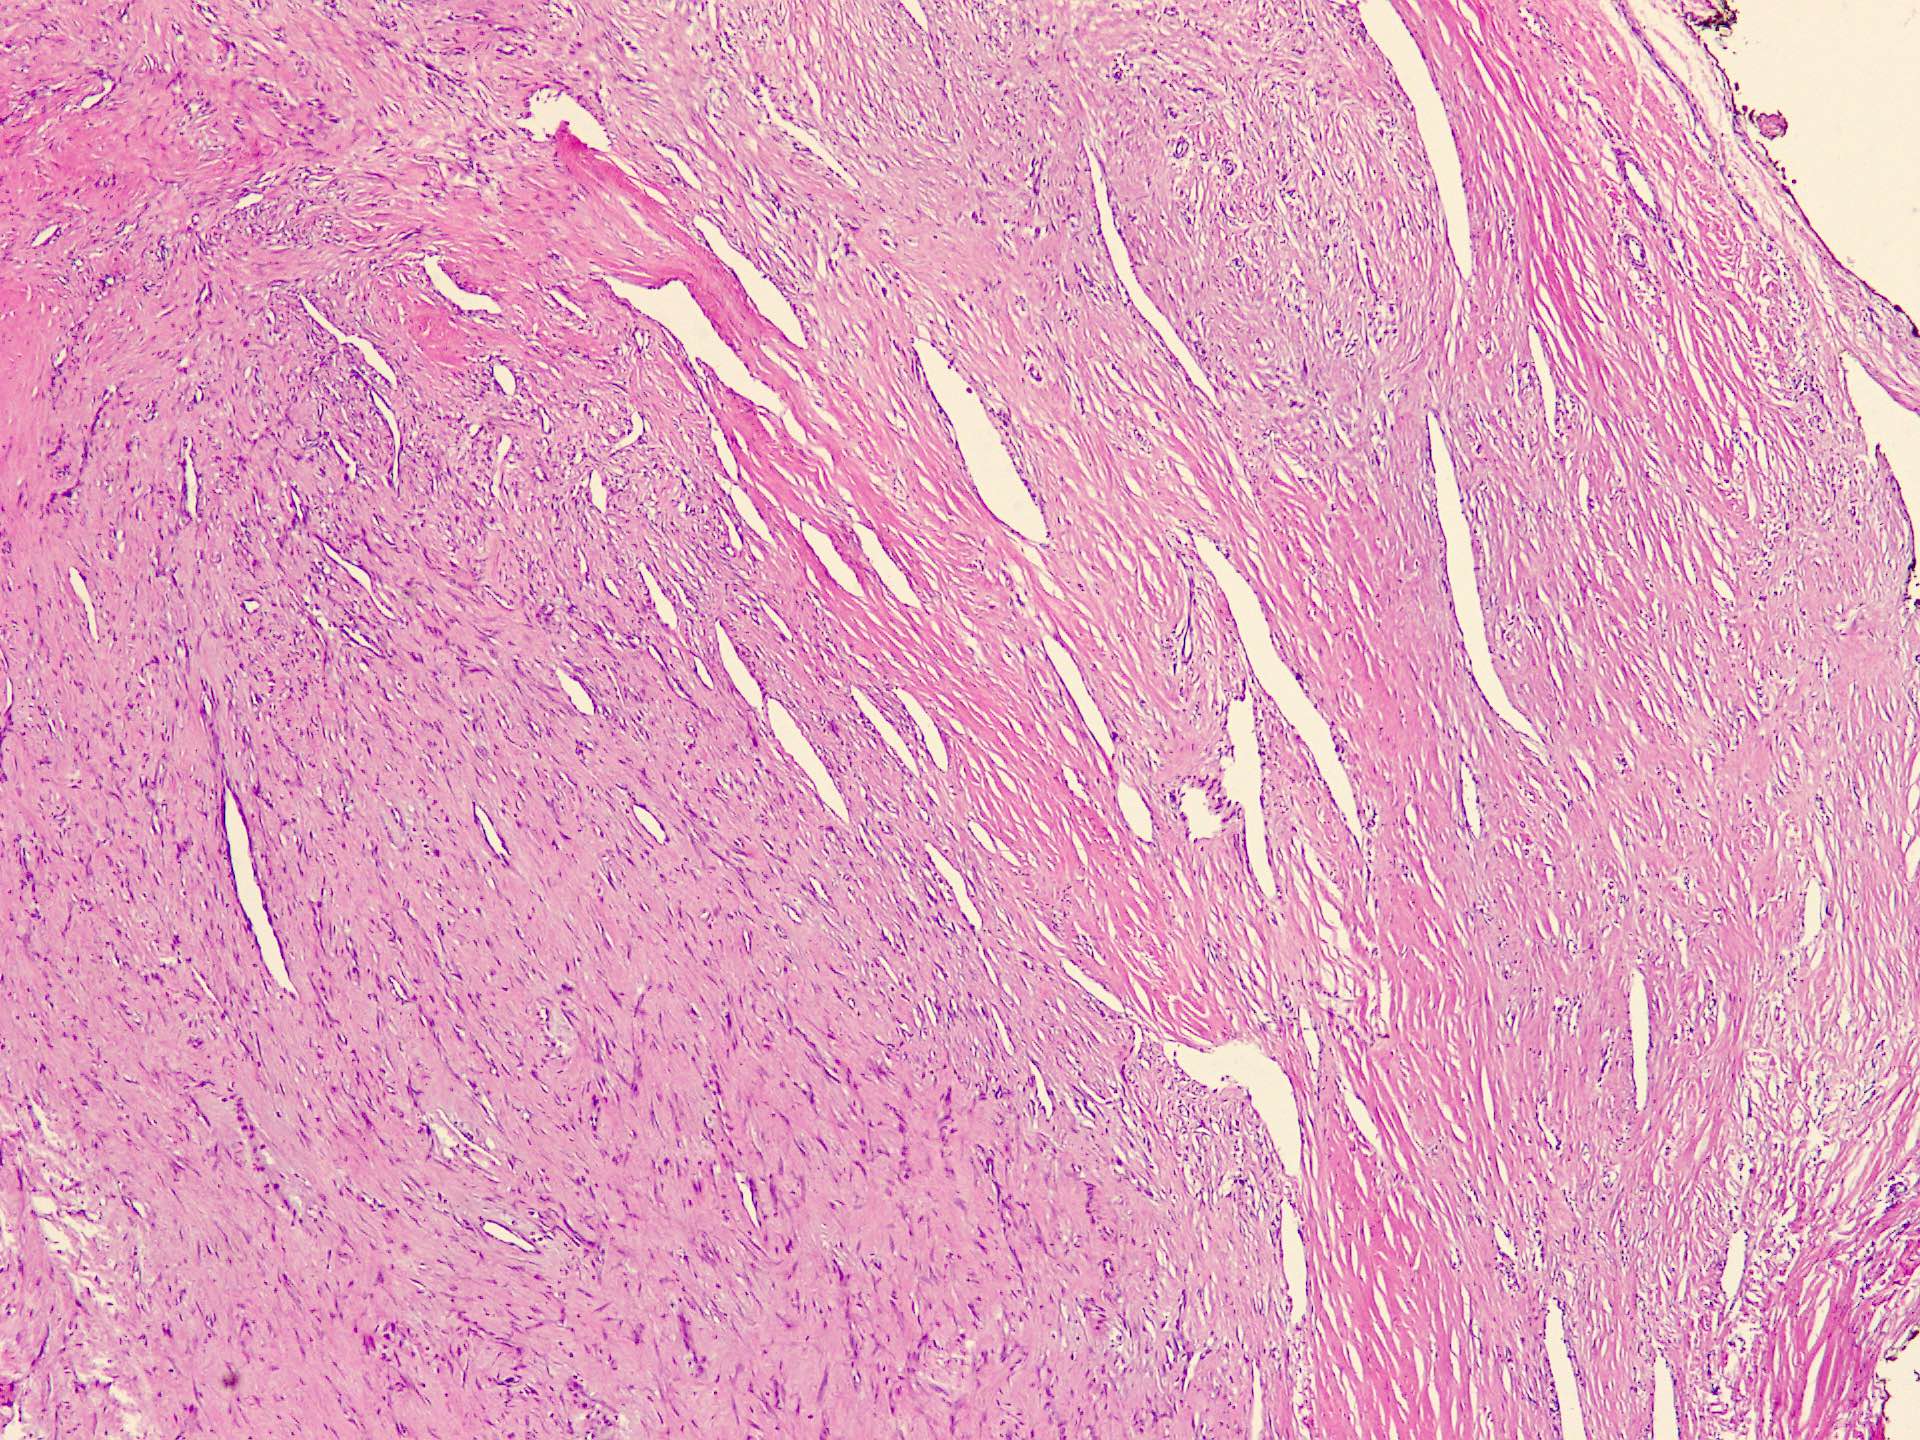

Microscopic (histologic) description

- Well circumscribed tumor of variable cellularity

- Cellularity mostly higher at tumor edges

- Bland spindle cells in a collagenous background

- Tumor has characteristic thin walled slit-like vessels

- Degenerative changes like myxoid / cystic change, osseous / chondroid metaplasia can be seen

- Bizarre pleomorphic cells can also be present

- Mitotically inactive

- Necrosis not present

- Cellular variant of fibroma of tendon sheath also exists; it overlaps morphologically with nodular fasciitis and fibrous histiocytoma (Cancer 1979;44:1945)

Microscopic (histologic) images

Contributed by Nasir Ud Din, M.B.B.S.

- Comment: Histology showed a well circumscribed, variably cellular lesion composed of bland spindle cells having regular nuclei arranged in sheets and fascicles. Thin walled vessels are present. The background is collagenous.

A 32 year old man has had painless swelling in the palm of his hand for 6 months. It was excised and the histology is shown in the above image. What is the most likely diagnosis?